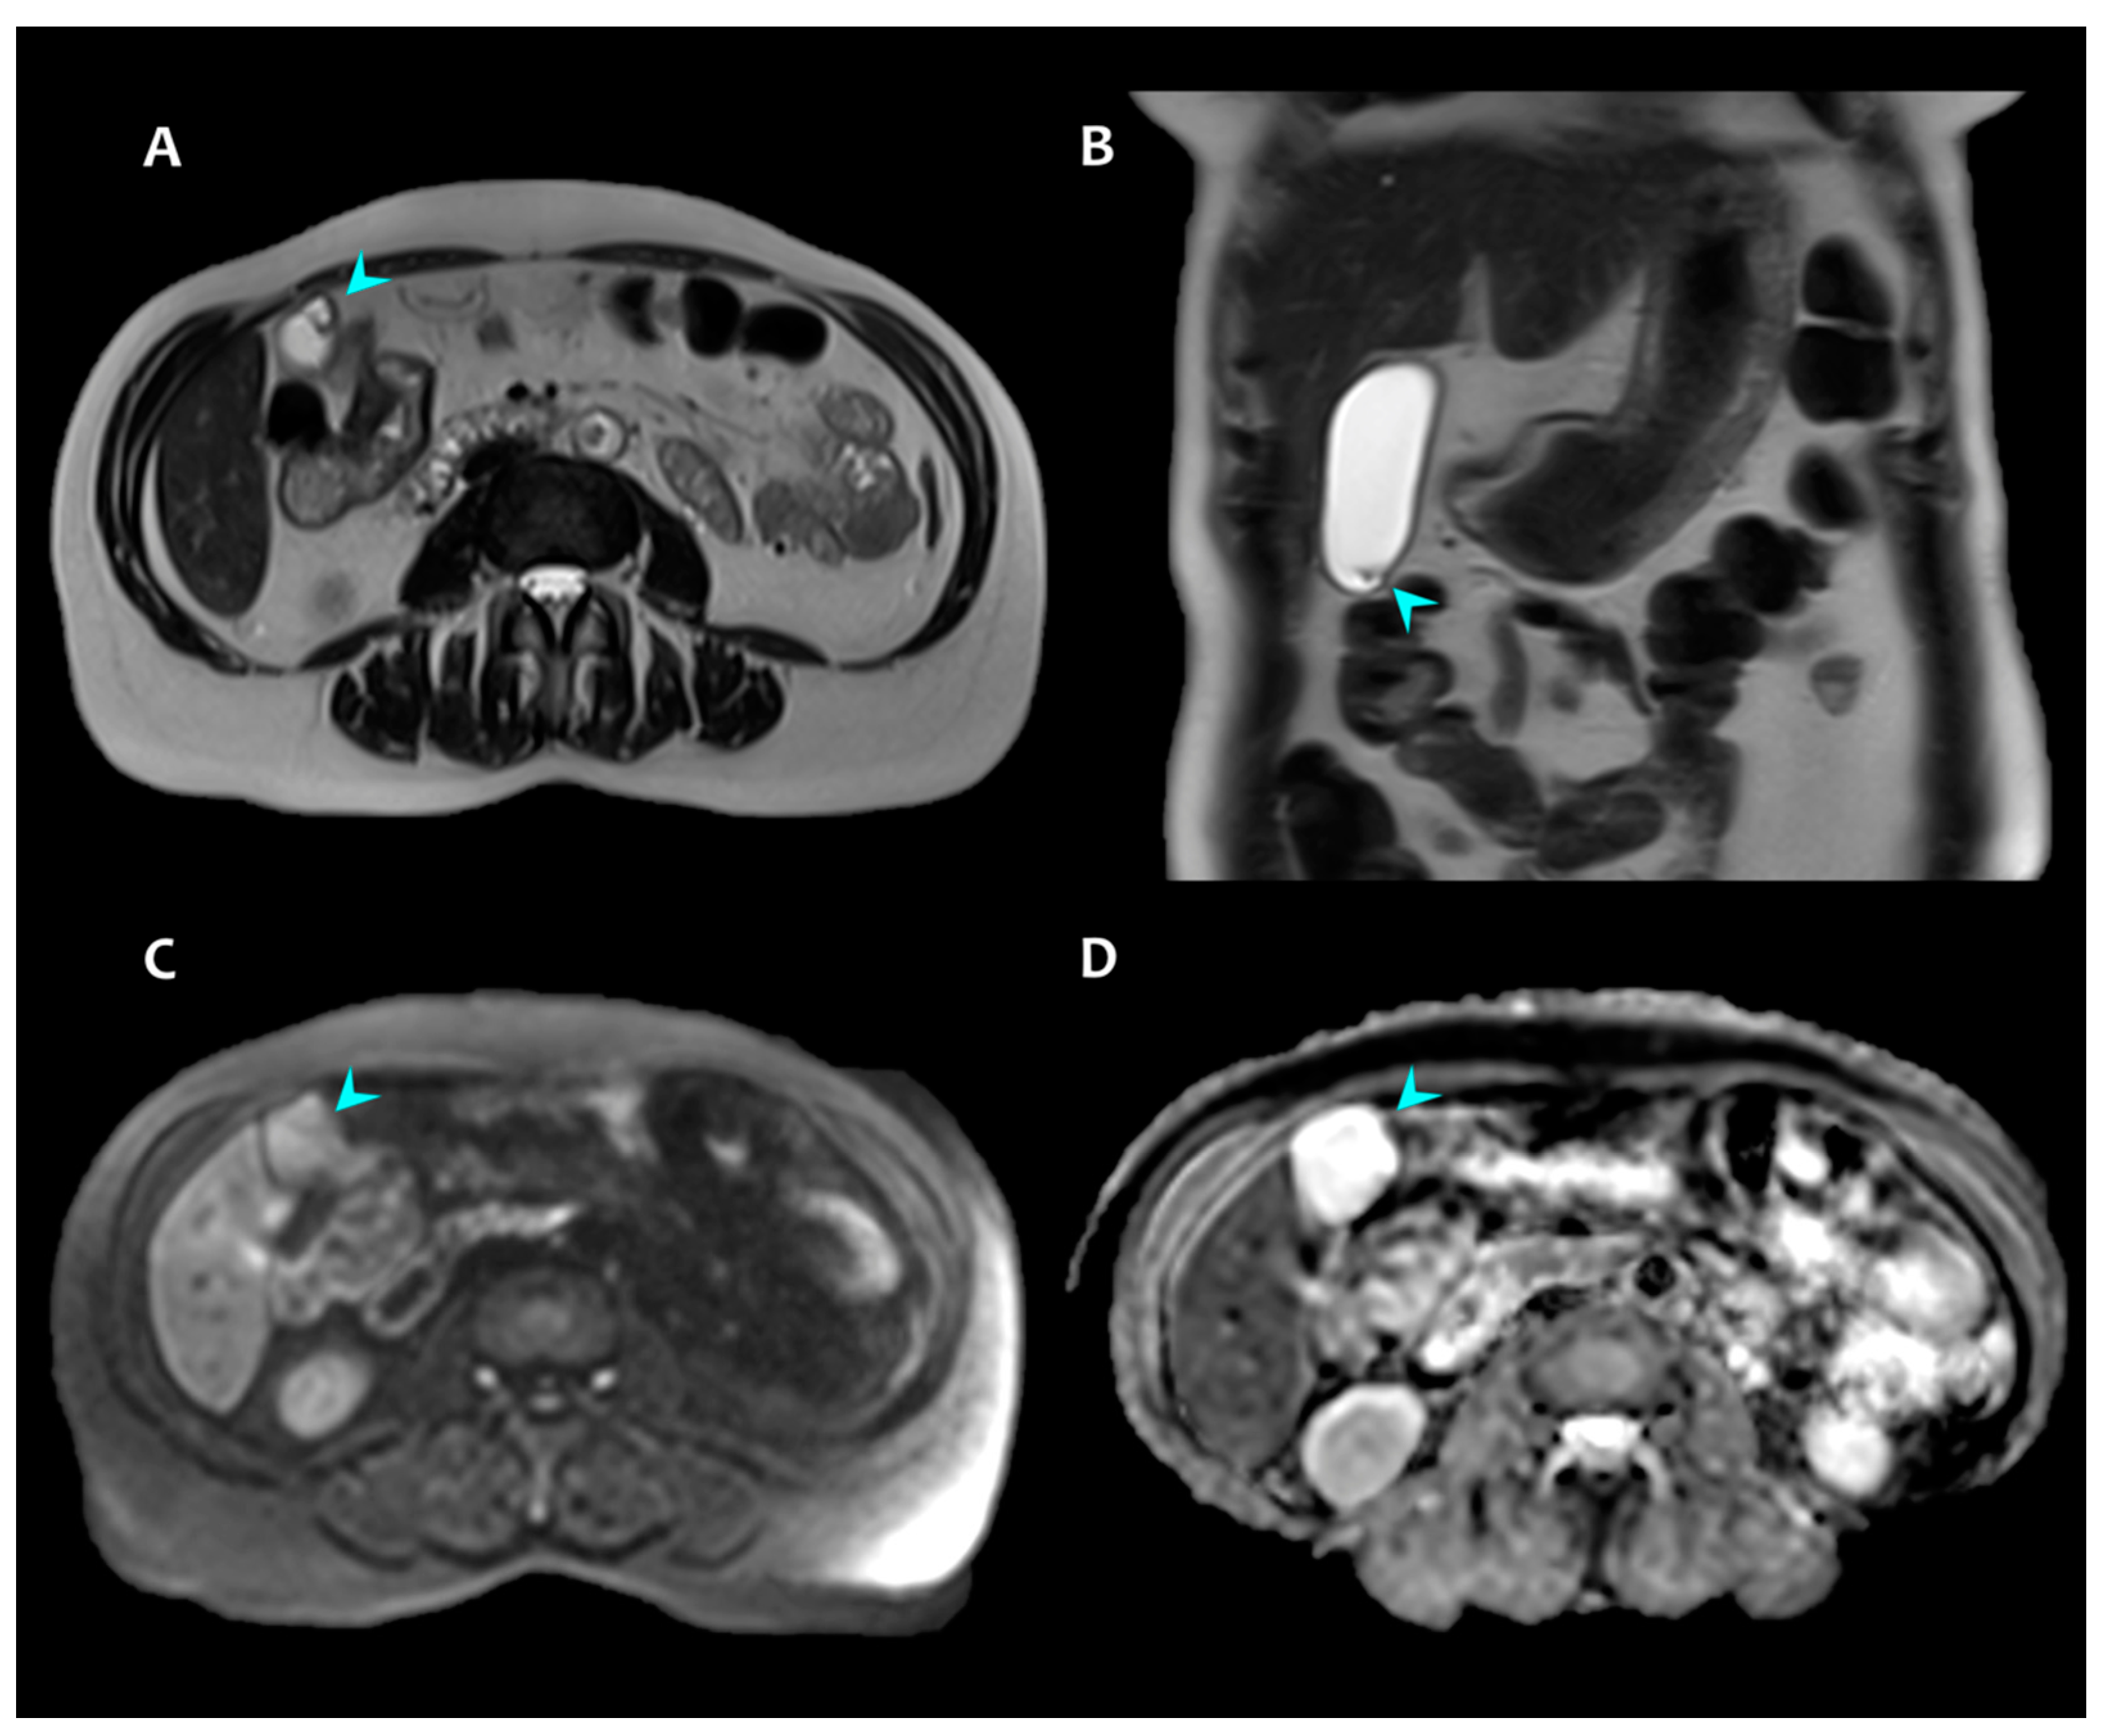

3. Presentation of Case #2